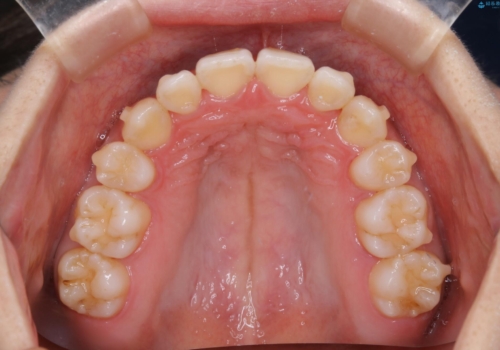

- 元々は海外でワイヤー矯正を行っていたが、コロナ禍で海外への往来が難しくなり、治療を中断せざるを得なくなってしまった方です。

ご本人のご希望により、インビザラインによる治療を行いました。

ブラケット除去直後に目立っていた下顎前歯部の大きなブラックトライアングルもあまり目立たなくなり、大変喜んでいただけました。